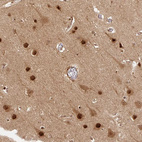

Immunohistochemical staining of human cerebral cortex, cervix, uterine, heart muscle and testis using Anti-PSMD1 antibody HPA036737 (A) shows similar protein distribution across tissues to independent antibody HPA036736 (B).